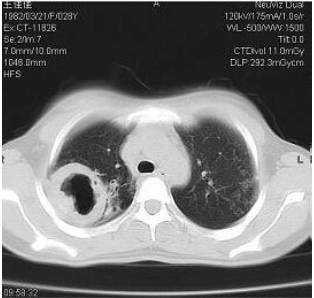

8.急性感染性肺部疾病:如肺脓疡,在空洞周围必然形成大量浸润炎性病变,空洞内可有液平。临床上应有急性症状如高热、咳黄脓并有臭味痰液,一旦进入慢性阶段,空洞仍可存在,周围炎症可吸收.

3.肺脓肿:急性肺脓肿的壁主要为炎性渗出病变,慢性肺脓肿的壁以纤维组织占主要成分。肺脓肿发生于肺炎后、吸入性及由肺外蔓延的病变,后者见于阿米巴肺脓肿。

(一)肺炎

1.急性肺炎合并肺脓肿:有的大叶性肺炎可合并急性肺脓肿。X线及CT表现为肺叶或肺段实变影像内的透亮影及气液平面。空洞一般较大,主要病原菌为肺炎双球菌。引起类似影像的其他疾病有某些革兰氏阴性杆菌,如克雷白杆菌等并发的肺脓肿,多见于免疫损害的患者。